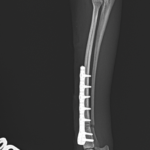

橈骨固定術 #270 極小犬(1.4kg)の橈骨固定術依頼です。骨幅3.8mmに対して1.2 Titanium Locking Plateと自家海綿骨移植を実施しています。初期固定強度を担保するために、外固定を併用しながらしばらくは安静が必要です。 症例カテゴリー 放射線治療整形外科軟部組織外科脳神経外科内科腫瘍外科救急・集中治療リハビリテーション科腫瘍内科内視鏡科脳神経科呼吸器外科中医・漢方猫の腎移植循環器科